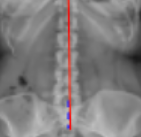

Coronal Balance

Apical Vertebral Rotation (AVR) - Nash-Moe classification

Trunk Shift